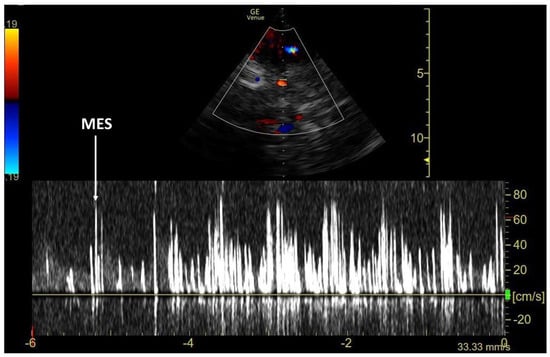

3.1. TCCD MES-Positive Case 1

3.2. TCCD MES-Positive Case 2

3.3. TCCD MES-Positive Case 3